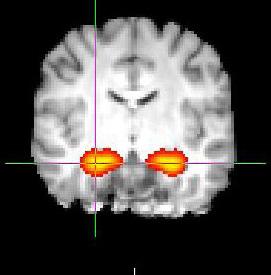

Study Finds Nicotine Changes Marijuana’s Effect on the Brain

Approximately 70% of marijuana users also smoke tobacco, yet few studies have included tobacco users in marijuana research. Center for BrainHealth’s Francesca Filbey, Ph.D., Director of Cognitive Neuroscience of Addictive Behavior, and her team recently published a study in the journal Behavioural Brain Research, exploring the effects on the brain among marijuana users who also use nicotine. The study found an unexpected relationship between the size of the hippocampus, a region of the brain associated with memory and learning, and memory performance in individuals who use both substances; the smaller the hippocampal size, the greater the memory function compared to others in the marijuana and nicotine-using group. The team also found an association between numbers of cigarettes smoked per day; the greater the number, the smaller the hippocampus and the better the memory performance. In contrast, hippocampal size of non-users predicted a direct relationship to memory function; the smaller the hippocampus, the poorer the memory performance. There were no significant associations between hippocampal size and memory performance in individuals who only use tobacco or only use marijuana. “We have always known that each substance is associated with effects on the brain and hypothesized that their interaction may not simply be a linear relationship. Our findings confirm that the interaction between marijuana and nicotine is indeed much more complicated due to the different mechanisms at play,” said Dr. Filbey. “Future studies need to address these compounding effects of substances.”